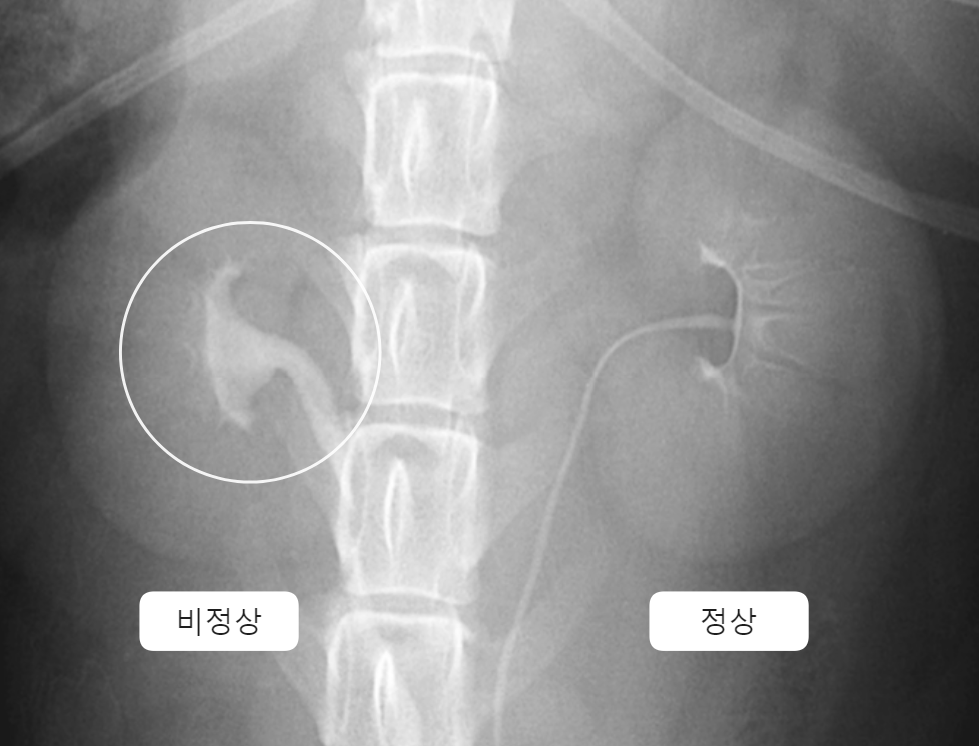

| Contrast radiography _Pyelonephritis | (contrast = ์กฐ์์ ์ฌ์ฉ) |

![]() | - Mild to moderate pyelectasia (์ ์ฐํ์ฅ) - Distortion of renal pelvis (์ ์ฐ ๋ณํ) |